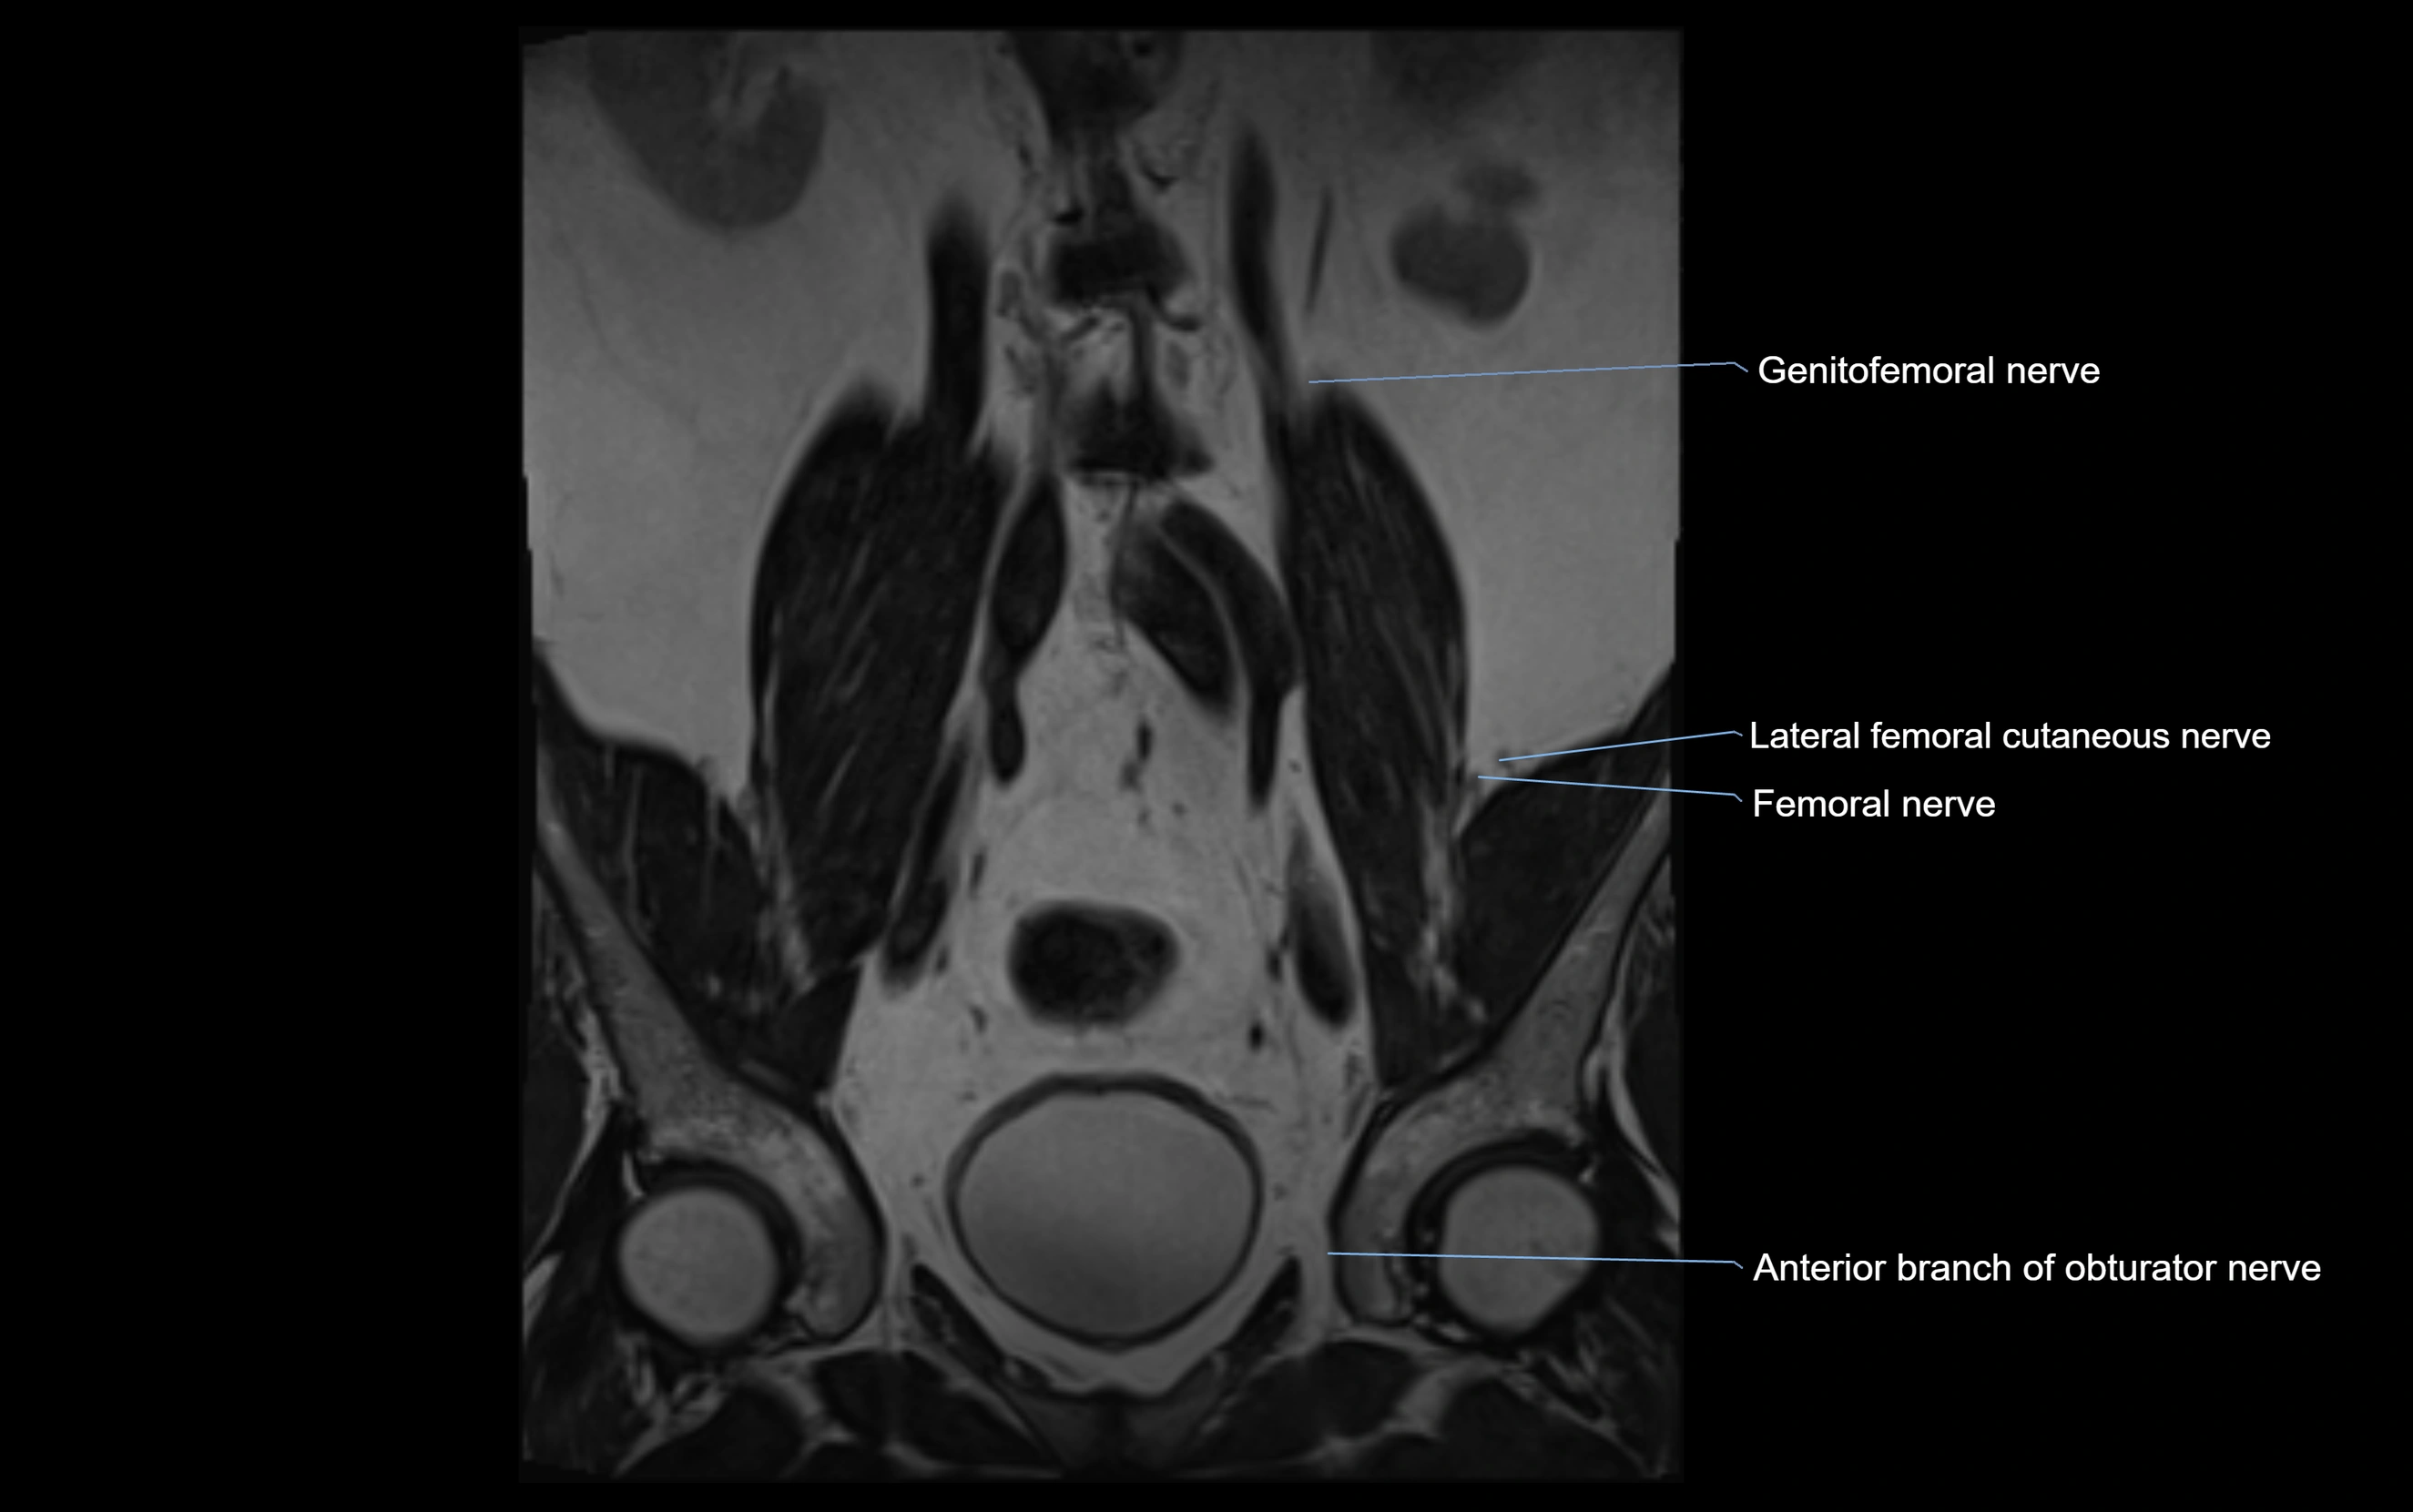

MRI image

image